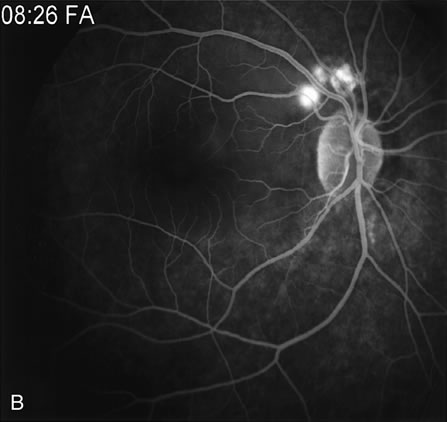

FA is also useful in characterizing two other subgroups of CNV: retinal angiomatous proliferation (RAP)8–16 and polypoidal choroidal vasculopathy (PCV).17–50 RAP begins in the deep retinal complex, forming intraretinal neovascularization (IRN), which may subsequently progress to extend beneath the neurosensory retina, forming subretinal neovascularization (SRN), and a vascularized PED.8 In the later phases of the process there may be a retinal-choroidal anastomosis (RCA). Clinical features of RAP include intraretinal hemorrhages, cystoid macular edema, and associated vascularized PED. FA is useful in revealing the presence of the angiomatous intraretinal vascular complex and the extension of the associated PED (Figs. 12 and 13). However, other diagnostic techniques such as indocyanine green (ICG) angiography, and optical coherence tomography (OCT) may be able to better demonstrate the presence of the RAP lesion.

Fig. 13. A. Early-phase Fluorescein angiography demonstrating the presence of an intraretinal angiomatous lesion (arrow). There is an associated pigment epithelium defect (PED), which is still hypofluorescent. B. Late-phase fluorescein angiography shows leakage from the retinal angiomatous proliferation (RAP) lesion and polling of dye into the PED. C. Indocyanine green angiogram of the same eye better demonstrates the presence of a hot spot corresponding to the RAP lesion. The PED remains hypofluorescent. D.Optical clearance tomography image demonstrates the presence of a serous PED and of intraretinal neovascularization.